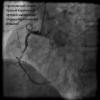

anthony Опубликовано 7 июня, 2014 Автор Жалоба Share Опубликовано 7 июня, 2014 Ну, если выполнить срочную операцию во время развивающегося инфаркта миокарда - можно спасти жизнь. Или нет? конкретно сегодняшний случай.пациет 62 лет длительное время болеет стенокардией напряжения. сегодня в 9 утра появлись жгучие боли,терпел, вызвал скорую помощь уже в обессиленном состоянии,на ЭКГ изменения свидетельствующие за начало развития острого инфаркта миокарда, объективно, бледный, давление систолическое 100 мм рт.ст - близко к кардиогенному шоку, обессиленный, жжение за грудиной.на фото видно атеросклеротическую бляшку которая на 99% закрывает просвет артерии и препятсвует току крови.именно данный стеноз вызвал прединфарктное состояние,был установлен стент в место стеноза, через 1 час пациент: ЭКГ пришло в норму, уже после транспортировки в палату интенсивной терапии. отмечает улучшение состояния, давление 130 х 90 мм.рт.ст. болевой синдром стих.в данном случае удалось предотвратить обширный инфаркт миокарда. movie00002.wmv movie00003.wmv Ссылка на комментарий Поделиться на другие сайты More sharing options...